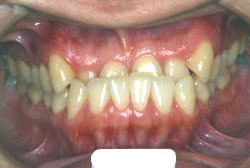

凸凹な歯並びのことを叢生といいます。矯正歯科に来院する患者様の主訴の中で、最も多いのが「配列の凸凹を真っ直ぐにしたい」というものです。歯の大きさと顎の大きさの調和がとれていないことが原因です。

凸凹を主体としたケースの場合、当院の平均治療期間は18ヶ月ですので、このケースは少し長めに経過しました。理由の一つは凸凹の程度がかなり重症だったと言うことですが、もう一つは、右下第2大臼歯が45度くらい前傾していたため、それを整直化させるために時間を要したと考えています。いずれにしても最終結果は大変よい状態と思います。

治療前は並びが乱れて見た目が悪いというのはもちろん問題ですが、歯科医学的に一番困るのは噛み合わせが悪いという点です。上下の犬歯(3番目の歯)は、上下的に離れた位置にあるため接触することができません。つまり歯としては存在していても、歯としては機能していないということです。